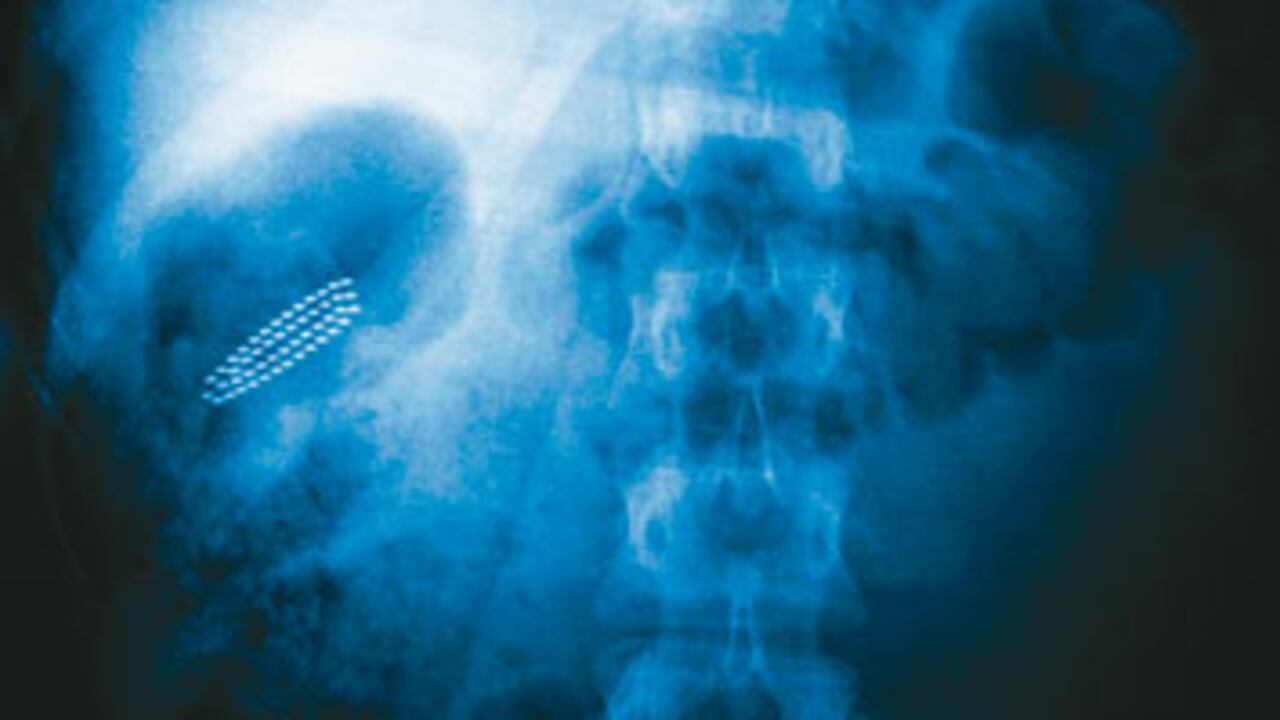

Como mi familia veía que me iban a dejar morir, un cuñado con un contacto en la emisora Radioacktiva llamó y contó el caso. De inmediato empezaron a echar la noticia, y terminaron enviándome al San Vicente de Paúl. Allí, por fortuna, lograron extraerme el cepillo por medio de una sonda como de endoscopia, y no fue necesario abrirme el estómago, que era lo que iban a hacer.